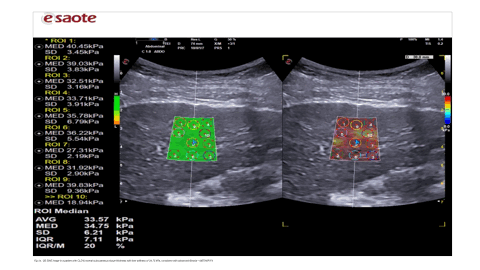

https://doi.org/10.59667/sjoranm.v26i1.16

Akib Arfee1, Omair Ashraf Shah1, Asif Iqball2, Afshana Bashir3, Aaqib Manzoor*1

¹Department of Radiodiagnosis and Imaging, Govt. Medical College Srinagar, India

2Department of Gastroenterology and Hepatology, Govt. Medical College Srinagar, India

3Department of Pathology, Govt. Medical College Srinagar, India

2D SWE matches Fibroscan’s accuracy but with fewer failures and advantage of real time anatomical guidance, making it a viable alternative especially for obese or ascitic CLD patients